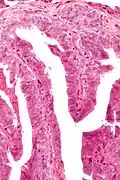

| Micrograph of a papillary hidradenoma with papillary structures; fragmented overlying epidermis is at the top of the image. H&E stain. | |

Microscopic histopathological analyses of papillary hidradenoma tumors typically reveal a nodule in the dermis, i.e. layer of skin between the epidermis and subcutaneous tissue. The tumor consists of complex patterns of interconnecting tubular and papillary (i.e. thin finger-like or frond-like) structures.[19] These structures are lined with glandular epithelial and myoepithelial cells. The glandular epithelial cells appear to be excessively proliferating in the ducts leading to the epidermis and show oxyphilic changes, (i.e. cytoplasm filled with large mitochondria, glycogen, and ribosomes) while the myoepithelial cells often appear clear cell-like, i.e. have uncolored cytoplasm when stained with hematoxylin and eosin.[1] The histopathology of anogenital and ectopic papillary hidradenomas are similar to each other.[7][9][15][18]